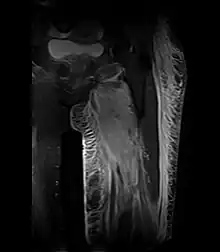

Creatine kinase may be normal or increased probably depending upon the stage of the condition when sampling is undertaken. ESR is elevated. Planar X-ray reveals soft tissue swelling and may potentially show gas within necrotic muscle, Bone scan may show non specific uptake later in the course. CT shows muscle oedema with preserved tissue planes (non-contrast enhancing). MRI is the exam of choice and shows increased signal on T2 weighted images within areas of muscle oedema. Contrast enhancement is helpful but must be weighed against the risk of Nephrogenic Systemic Fibrosis as many diabetics have underlying chronic kidney disease. Arteriography reveals large and medium vessel arteriosclerosis occasionally with dye within the area of tissue infarction. Electromyography shows non specific focal changes.